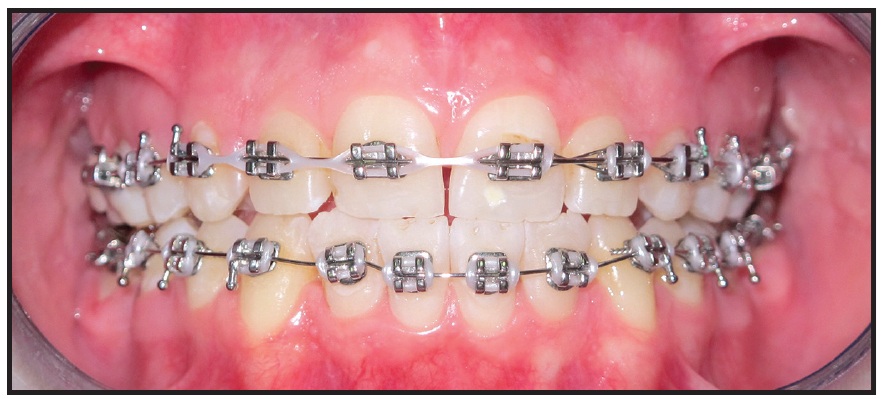

Roth-prescription .022" brackets* were bonded to the lower canines, first and second premolars, and second molars only; the lower anterior teeth were bypassed to prevent undesirable proclination (Fig. 3). The posterior teeth were discluded with glass ionomer cement to avoid occlusal interference. Leveling and alignment of the lower arch were initiated with a continuous .014" nickel titanium archwire, progressively increasing to .016" × .022" nickel titanium.

Fig. 3 Lower canines, first and second premolars, and second molars bonded, with anterior teeth bypassed to prevent proclination. B. Bite raised to avoid occlusal interference.